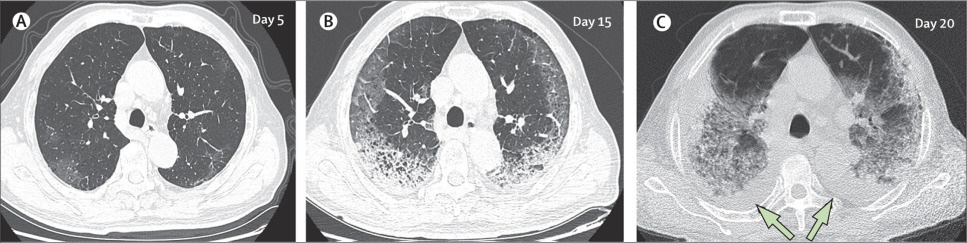

virus corona lan rong anh 1

Đây là hình ảnh chụp CT phổi của Tiger Ye, một bệnh nhân 21 tuổi tại Vũ Hán. Trong 3 tuần, Tiger miêu tả cuộc sống của mình như "chết đi sống lại" với những cơn ho đến nổ phổi, toàn thân đau nhức. May mắn, bệnh nhân này đã qua khỏi tình trạng nguy kịch và đã được xuất viện về nhà theo dõi tiếp từ ngày 12/2. Ảnh: Bloomberg.

Đây là CT phổi của một bệnh nhân nam 77 tuổi (ở Trung Quốc) trong gần 3 tuần điều trị. Đáng tiếc, tình trạng của bệnh nhân nguy kịch, không qua khỏi do sức tàn phá mạnh của virus corona bên trong phổi. (A) - ngày thứ 5, sau khi khởi phát triệu chứng: các mảnh mờ đục bắt đầu loang lổ, ảnh hưởng đến nhu mô phổi hai bên, dưới màng cứng. (B) - ngày thứ 15, các đốm trắng hình lưỡi liềm đã chiếm lấy cả hai phổi, xuôi theo võng mạc phía sau và tập trung ở đáy. (C) - ngày 20, các tổn thương mở rộng ra hai bên phổi, đốm trắng gần như chiếm được cơ quan này và xuất hiện tình trạng tràn dịch màng phổi hai bên (mũi tên). 10 ngày sau lần quét này,bệnh nhân tử vong. Ảnh: The Lancet.